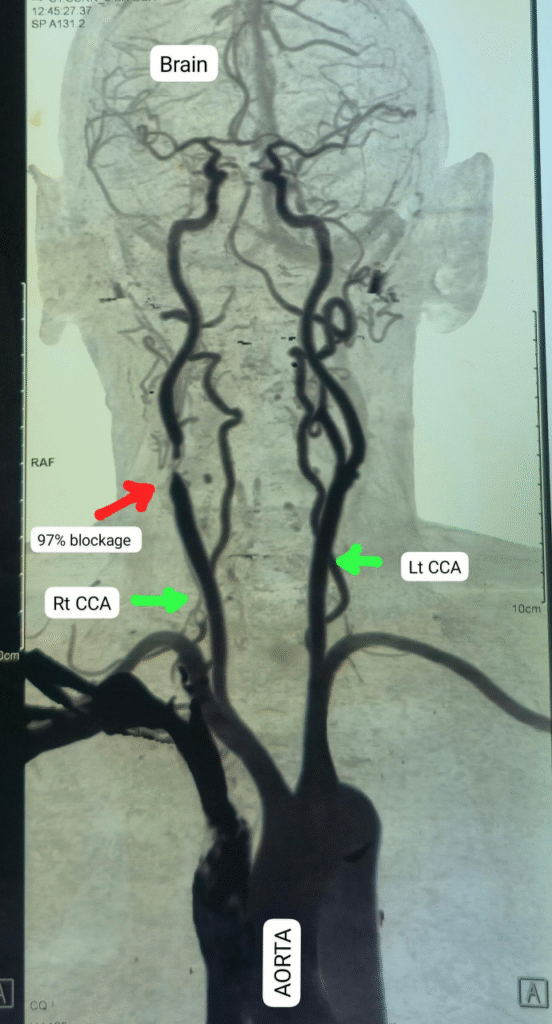

The patient had a 95% blockage in his right carotid artery—a vital blood vessel supplying oxygen-rich blood from the neck to the brain. The complex procedure, known as carotid endarterectomy, was conducted by Dr. Krishnakant Sahu, Head of the Department of Heart, Chest, and Vascular Surgery, and his team.

The elderly patient from Balaghat had been suffering for two years with recurring strokes, dizziness, blurred vision in one eye, and hearing loss. A detailed examination, including carotid CT angiography, revealed the severe blockage in the artery, which was disrupting blood flow to the brain and putting him at high risk for a major stroke.

To maintain uninterrupted blood flow to the brain during the procedure, the surgical team used a specialized device called a carotid shunt. Once the blockage was removed, the artery was repaired using a bovine pericardium patch, restoring normal blood circulation. The surgery was successful, and the patient is now recovering well and ready for discharge.